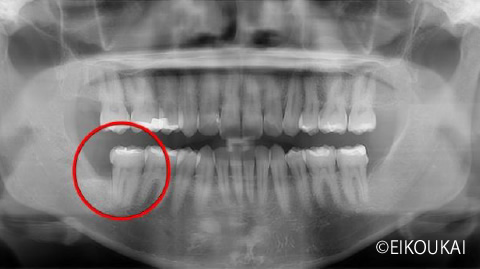

親知らずの虫歯トラブルをスピード解消。CT診断に基づいた安全な抜歯症例

治療内容 汚れが溜まり、虫歯があり右下の親知らずを抜歯しました。 金額 埋伏抜歯5,120円 CT 4,400円 治療期間 1日 通院回数 1回 リスク/副作用 抜歯後にしびれが出ることや、まれに腫れや痛みが長引くことがあります。

| 治療内容 | 汚れが溜まり、虫歯があり右下の親知らずを抜歯しました。 |

| 金額 | 埋伏抜歯5,120円 CT 4,400円 |

| リスク/副作用 | 抜歯後にしびれが出ることや、まれに腫れや痛みが長引くことがあります。 |